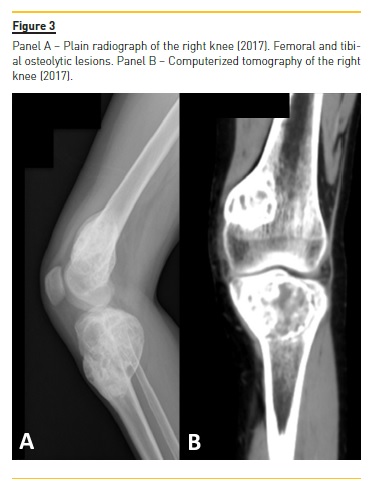

She developed CKD-MBD and maintained marginal control of PTH, calcium and phosphorus levels throughout the following years, mainly in association with low therapeutic adherence, leading to high PTH levels, frequently >1000 pg/mL. In 2013, four years after initiation of renal replacement therapy and three years after starting peritoneal dialysis, she presented right knee pain with limited range of motion which gradually worsened for two months. At that time PTH value was 1119 pg/mL. Plain radiographies revealed lytic lesions in distal femurs, proximal right femur, and right proximal tibias (Fig. 1). Computerized tomography (Fig. 2) confirmed the osteolytic bone lesions and revealed another lesion with the same features at the right iliac. The lytic lesion at right neck femur was 5.5 cm along its longitudinal axis and presented a thinned inner cortex. Computed tomography guided bone biopsy from proximal tibia was performed and documented proliferation of fibrous connective tissue and hemosiderin deposits with disperse multinucleated giant cells. These findings were compatible with brown tumors associated with severe hyperparathyroidism.